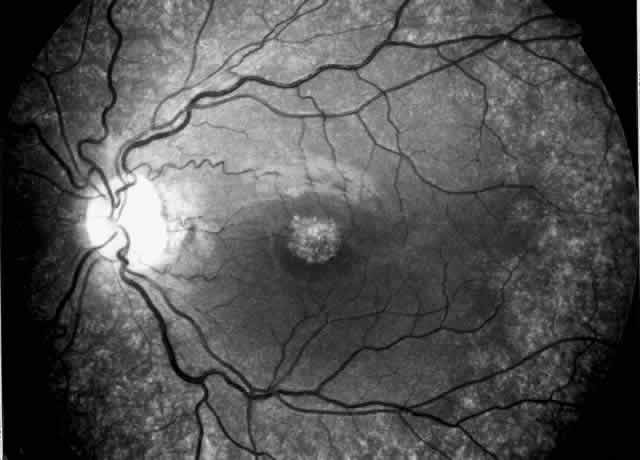

Drusen-like lesions and retinal pigment epithelium damage have also been recognized as a feature of MPGN type II.72–79 In a fluorescein angiographic study of 26 patients who had biopsy-proven MPGN type II, specific fundus lesions were identified in 24 patients (92%).79 Two adolescents with a history of renal disease of 13 months and 2 months had normal fundi. Small-sized lesions similar to small hard drusen were observed in all 24 patients with a history of renal disease lasting for 16 months or more (Fig. 6). In all 15 subjects with a history of renal disease of at least 12 years, larger drusen-like lesions were also noticed. In all 11 patients with renal disease persisting for 18 years or more, drusen occupied most of the fundus and areas of geographic atrophy were seen as well. Foci of new vessels and disciform scarring were observed in eight eyes of five patients with a renal history of 15 years or more (Fig. 7). Most eyes that did not show subretinal neovascularization had normal or nearly normal vision and visual fields. Three patients, however, exhibited ocular symptoms, which were related to pronounced macular atrophic changes, hypertensive retinopathy, and cataracts. The type of fundus lesions was statistically correlated (p<0.0001) with the duration of the renal disease, but not with age, sex, or renal insufficiency. Fundus changes between first and last visit as well as cross-sectional studies suggest a slow progression of retinal disease, which is probably independent of treatment and age of the patient.77–79

Fig. 6. Specific fundus lesions of membranoproliferative glomerulonephritis type II in a 12-year-old child with renal disease since the age of 3 years. The fluorescein angiogram shows numerous small lesions similar to hard drusen. (Leys A, Vanrenterghem Y, Van Damme B et al: Fundus changes in membranoproliferative glomerulonephritis type II: A fluorescein angiographic study of 23 patients. Graefes Arch Clin Exp Ophthalmol 229:406, 1991)

Fig. 7. Fluorescein angiographic changes in a 32-year-old patient with renal signs of membranoproliferative glomerulonephritis type II since the age of 9 years. Numerous small and larger drusen-like lesions, atrophic changes, and a small infrafoveolar subretinal neovascular membrane that was successfully treated with argon laser coagulation can be seen. (Leys A, Michielsen B, Leys M et al: Subretinal neovascular membranes associated with chronic membranoproliferative glomerulonephritis type II. Graefes Arch Clin Exp Ophthalmol 228:499, 1990)